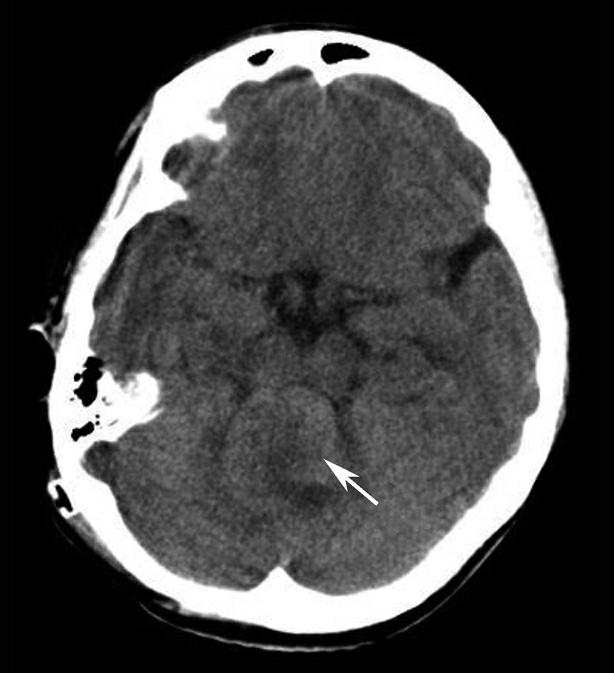

图1-2-20 环池闭塞

右侧颞叶脑内大血肿(★),产生严重的占位效应,环池受压闭塞(箭),脑疝形成